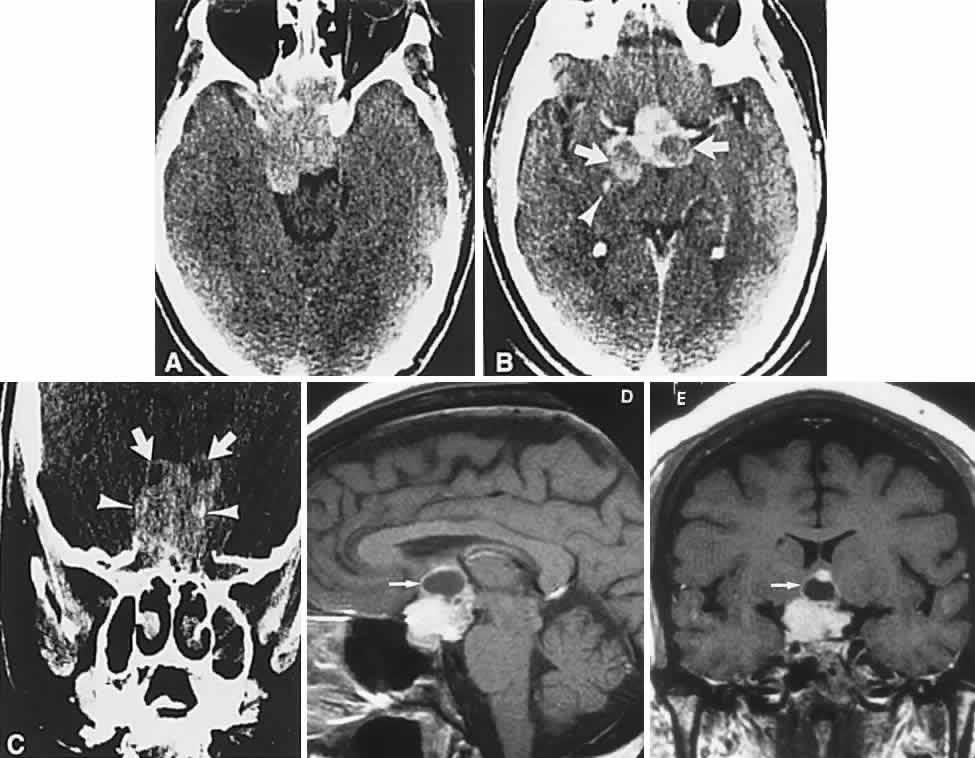

Fig. 3. Neuroimaging of pituitary adenomas. A. Axial computed tomography (CT) section shows a round tumor mass filling the suprasellar cistern; ring enhancement (arrows) indicates subcapsular hemorrhage. B. Contrast-enhanced coronal CT section through a large invasive adenoma. Note encasement of the carotid artery (arrows) and the position of the middle cerebral artery above (arrowheads). C. Axial CT section shows lateral expansion into the cavernous sinuses (white arrows) and a necrotic cyst (black arrow). D. Subfrontal superior extent of the mass. Note the middle cerebral arteries. E. Magnetic resonance imaging of a large lobulated prolactinoma, with suprasellar extension. Note the distortion of the third ventricle (open arrows) and extension toward the temporal lobe (long arrow); the tumor has not involved the sphenoidal sinus (s). F. Chiasm (arrowheads) is draped on the superior surface of the tumor (TR, 550 milliseconds; TE, 26 milliseconds). G. Sagittal section shows suprasellar growth with the chiasm above (arrowheads); the sella (arrows) and sphenoidal sinus (s) are normal (TR, 850 milliseconds; TE, 26 milliseconds). H. Hyperintense signal (TR, 2000 milliseconds; TE, 60 milliseconds) indicates the partial cystic character. Sagittal (I) and axial (J) sections with head tilt to the right, in case of a large cystic adenoma with an interface level between newer blood (white arrow) and older blood (black arrow) (TR, 800 milliseconds; TE, 30 milliseconds). K. Signal difference is intensified (TR, 2100 milliseconds; TE, 80 milliseconds). L. Hemorrhage (bright signal, arrow) in a pituitary adenoma with headache and bitemporal field depressions. M. Without interventions, 2-month follow-up showed spontaneous involution, with normal pituitary gland (arrow), stalk, and chiasm.

Imaging of Pituitary Tumors

In addition to the radiologic implications mentioned previously, specific points should be emphasized. Contrast-enhanced CT and, especially, MRI have replaced all previous radiologic techniques in the detection and anatomic assessment of sellar and juxtasellar lesions. MRI has also the inherent advantage of using no radiation, nor does it require iodinated contrast injections. Although thin-section contrasted CT does indeed disclose most lesions, bone changes, and recent hemorrhage, MRI is superior in delineating distortions of optic nerves and chiasm, in displaying arteries, and in revealing fat, hemorrhage, or cyst (see Figs. 3E through M). Indeed, in a prospective study of normal volunteers, gadolinium-enhanced MRI disclosed pituitary adenomas (3 mm to 6 mm in diameter, i.e., microadenomas) in 10% of adults aged 18 to 60 years.66 T2-weighted fast spin-echo MRIs are currently the most precise sequence for demonstrating the optic nerves and chiasm, even when these structures are severely distorted by suprasellar tumor extension.67